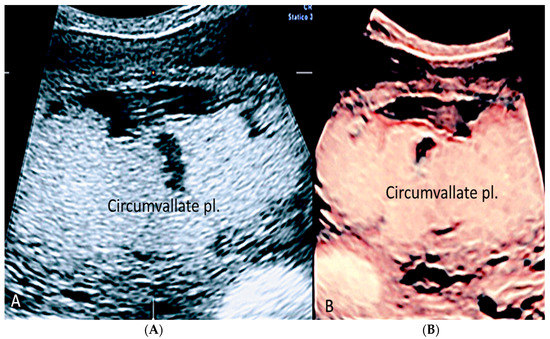

3.1.4. Circumvallate Placenta